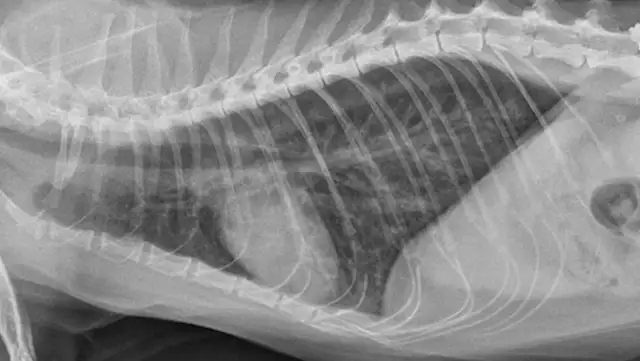

Mixed cardiac and pulmonary disease can exist in small animals with respiratory distress. For example, a dog may be presented with a history of mitral valve insufficiency but have clinical and radiographic evidence of aspiration pneumonia following a dental prophylaxis; or, a cat may present with a heart murmur and evidence of lower airway disease based on breathing pattern and thoracic radiographs (Figure 4; see image gallery above).